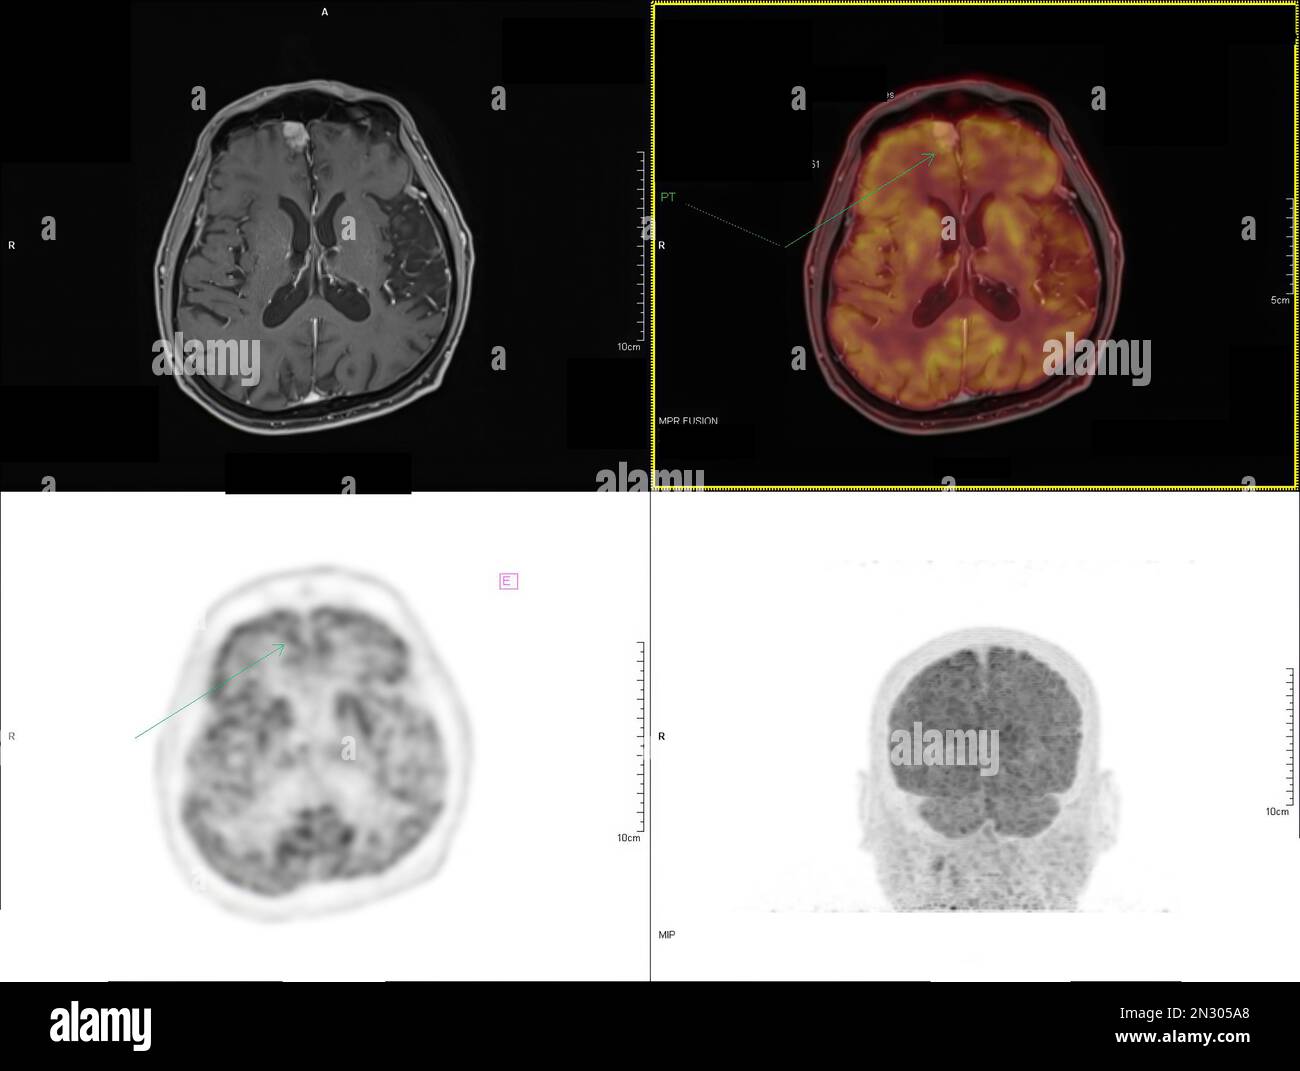

RF2N305A8–La tomographie par émission de positrons (TEP) CT scan utilise un médicament radioactif (traceur) pour montrer l'activité métabolique normale et anormale de tout le corps humain

RF2N305A6–La tomographie par émission de positrons (TEP) CT scan utilise un médicament radioactif (traceur) pour montrer l'activité métabolique normale et anormale de tout le corps humain

RF2N305G8–La tomographie par émission de positrons (TEP) CT scan utilise un médicament radioactif (traceur) pour montrer l'activité métabolique normale et anormale de tout le corps humain